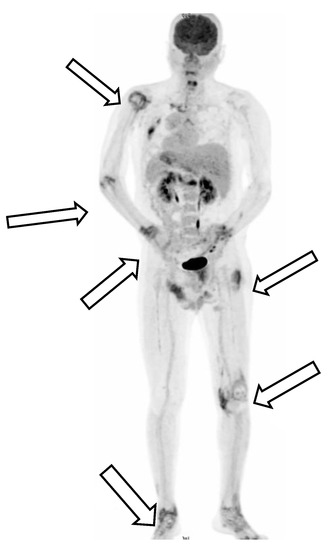

Background and Objectives: Thymomas are associated with a high frequency of paraneoplastic manifestations. Paraneoplastic syndrome (PNS) with thymoma presents a challenge to clinicians because of the need to decipher the association between the presenting symptoms and the underlying tumor. The condition most [...] Read more.

Background and Objectives: Thymomas are associated with a high frequency of paraneoplastic manifestations. Paraneoplastic syndrome (PNS) with thymoma presents a challenge to clinicians because of the need to decipher the association between the presenting symptoms and the underlying tumor. The condition most commonly noted in patients with PNS with thymoma is myasthenia gravis. Other common autoimmune diseases that may present as PNS include systemic lupus erythematosus, pure red cell aplasia, and Good syndrome. Seventy-six percent of patients with PNS-associated thymoma experience resolution of PNS after curing thymoma. Materials and Methods: A 37-year-old man with a two-month fever accompanied by polyarthritis accidently found thymoma after contrast computed tomography scans of his chest. He accepted Video assisted thoracoscopic surgery with resection of thymoma. Results: Fever and polyarthritis resolved after operation but recurred in five days due to cytomegalovirus viremia, which might be predisposed by previous antibiotics treatment before the diagnosis of thymoma. Conclusion: Patients with a thymoma also have a high frequency of PNS, and the most frequent condition found in patients with PNS-associated thymoma is myasthenia gravis. Fever with polyarthritis has been rarely reported as a symptom of PNS-associated thymoma. Here we reported an unusual case of PNS mimicking reactive arthritis with thymoma, as diagnosed based on the patient’s clinical progression, imaging examination, and laboratory tests. The patient died of his comorbidities, and his death may have been related to long-term antibiotic use and consequent intestinal dysbiosis. This challenging case may help to inform clinicians of the need for detailed work-up of fever with unknown origin in the presence of chronic polyarthritis to prevent the overdiagnosis of inflammatory arthritis or rheumatic disease and avoid further comorbidities. Detailed work-up should include the patient’s history of infections, inflammation, and malignant or nonmalignant tumors. Full article

Show Figures

Figure 1